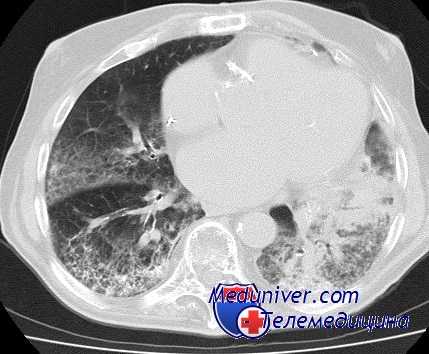

Первые же операции с ОВЧВ показали, что такой способ вентиляции обеспечивает адекватный газообмен и стабильную гемодинамику. Дальнейшие исследования подтвердили правильность этих наблюдений (Рис. 1).

Рис. 1. Параметры газообмена и гемодинамики при двулёгочной

традиционной вентиляции (ИВЛ),

однолёгочной традиционной вентиляции (ОИВЛ),

однолёгочной высокосокочастотной вентиляции (ОВЧВ).

Помещённые на рисунке 1 диаграммы отчётливо иллюстрируют преимущества ОВЧВ перед традиционными способами вентиляции. Наиболее существенные различия в регистрируемых параметрах отмечаются при однолёгочных вариантах вентиляции. ОВЧВ сопровождается достоверно лучшей оксигенацией артериальной крови при нормальных показателях РаСО2 и рН. И, хотя при однолёгочной традиционной вентиляции средние величины РаО2 указывают на отсутствие выраженной гипоксемии, следует учесть, что более чем у 1/3 наших пациентов (18 из 50) РаО2 находилось в пределах 80 мм. рт. ст. Это были преимущественно пациенты с сопутствующими лёгочными и сердечно-сосудистыми заболеваниями, то есть как раз те, операционный риск у которых наиболее высок.

При ОВЧВ отмечаются достоверно меньшие значения транспульмонального (Pes) давления, способствующие более высокому венозному возврату и сердечному выбросу.